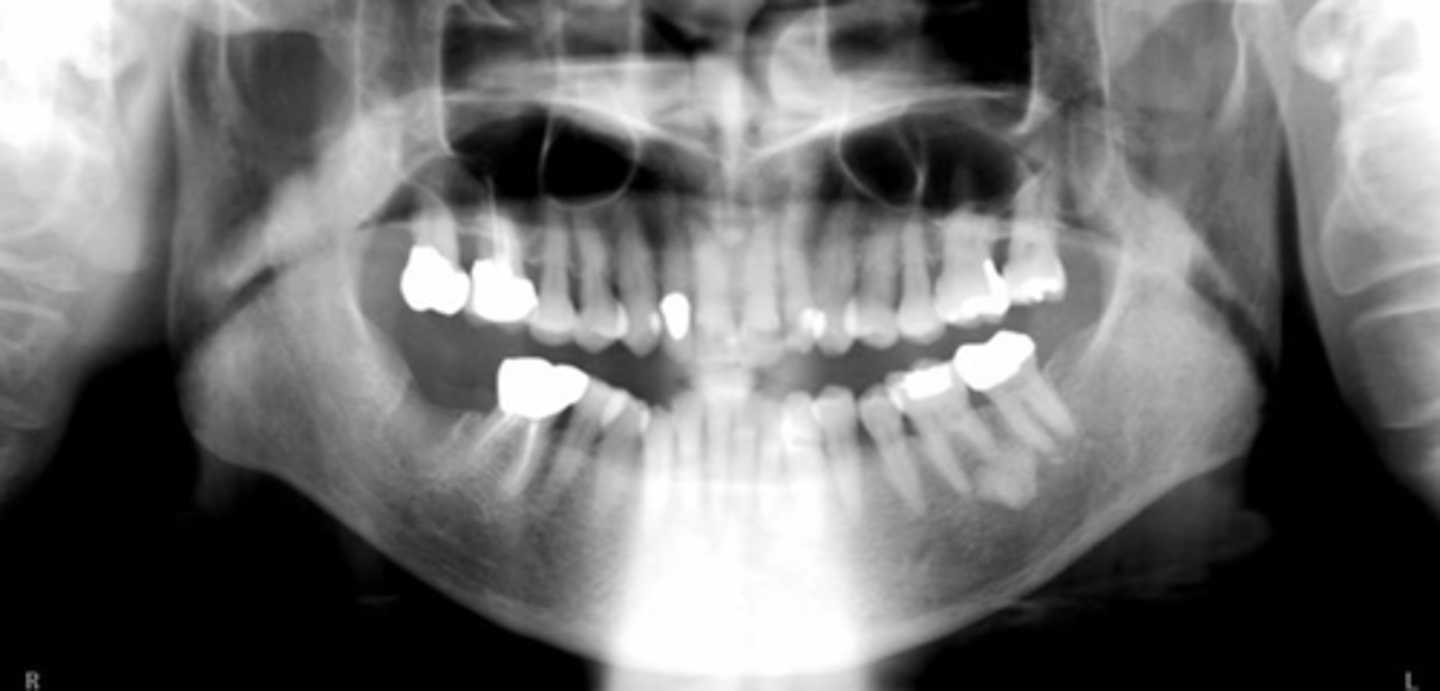

- patient didn't close all the way

- chin was down

- patient is too close to the film/receptor

What are the problems in this panoramic image?